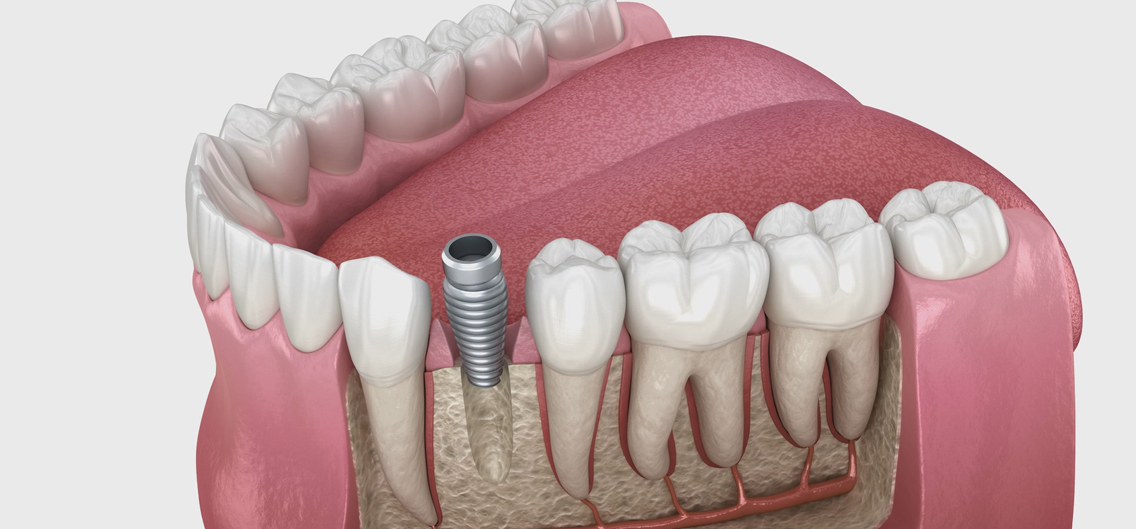

치조골에 임플란트 픽스처(뿌리 역할)를 정확하게 심는 단계로, 국소마취 하에 안전하게 진행됩니다.

임플란트와 턱뼈가 자연스럽게 결합되는 기간입니다. 이 과정은 안정적인 고정력을 형성하는 데 매우 중요합니다.

임플란트와 보철물을 이어주는 지대주를 부착하여 크라운을 올릴 기반을 마련합니다.

환자의 치아 모양·색상에 맞춰 맞춤 제작된 크라운을 부착해 자연스러운 심미성과 기능을 회복합니다.